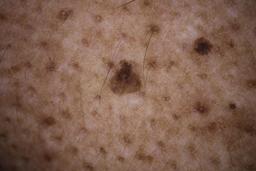

ISIC_6598546

Clinical

| Field | Value |

|---|---|

| age_approx | 60 |

| anatom_site_1 | Trunk |

| anatom_site_2 | Posterior trunk |

| concomitant_biopsy | False |

| dermoscopic_type | contact polarized |

| diagnosis_1 | Benign |

| diagnosis_confirm_type | single contributor clinical assessment |

| fitzpatrick_skin_type | VI |

| image_manipulation | instrument only |

| image_type | dermoscopic |

| lesion_id | IL_6711989 |

| patient_id | IP_8590441 |

| sex | male |